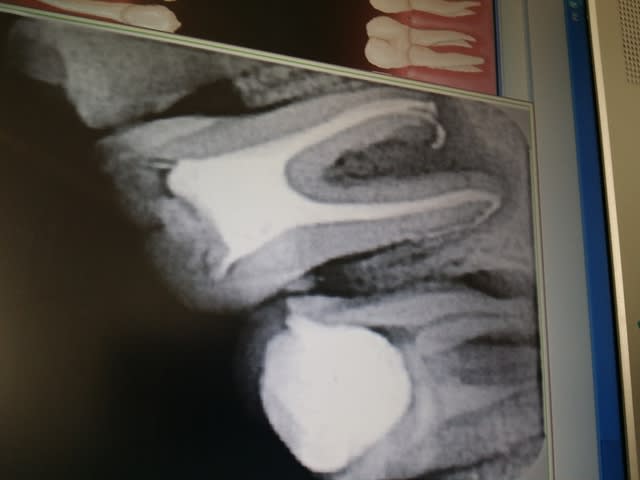

bonjour, j'ai eu en consultation un jeune chez qui je fais un bilan radio et je trouve cette magnifique endo sur une 36 qui ne s'en trouve pas moins asymptomatique.

J'explique au patient grâce à la radio que le traitement de racine est incomplet et qu'il faut le refaire si l'on veut sauver cette dent.

Je désobture tout cela irrigation à mort à l'hypochlorite et je me dis je passe par une séance à l'hydroxyde pour aseptiser la bête en sommeil... Qu'est ce que j'ai pas fait! il a passé un week end horrible et malgré l'amoxicilline en préventif c'est parti en cellulite énorme. J'ai réouvert la dent et du pus sortait à la pression par le canal distal. résultat j'ai laissé ouvert et augmentin. c'est franchement très souvent que ça part en rebond infectieux quand on touche ces daubes en sommeil. avez vous des trucs pour prévenir ces réactions ou alors suis je trop optimiste et je sors le davier la prochaine fois car j'ai peur que ça recommence après obturation à la gutta? merci pour vos avis et expériences